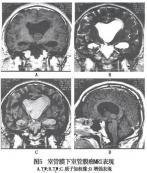

• 室管膜瘤

室管膜瘤來源于腦室與脊髓中央管的室管膜細胞或腦內白質室管膜細胞巢的中樞神經系統腫瘤。男多于女,多見于兒童及青年。疾病描述室管膜瘤來源于腦室與脊髓中央管的室管膜細...